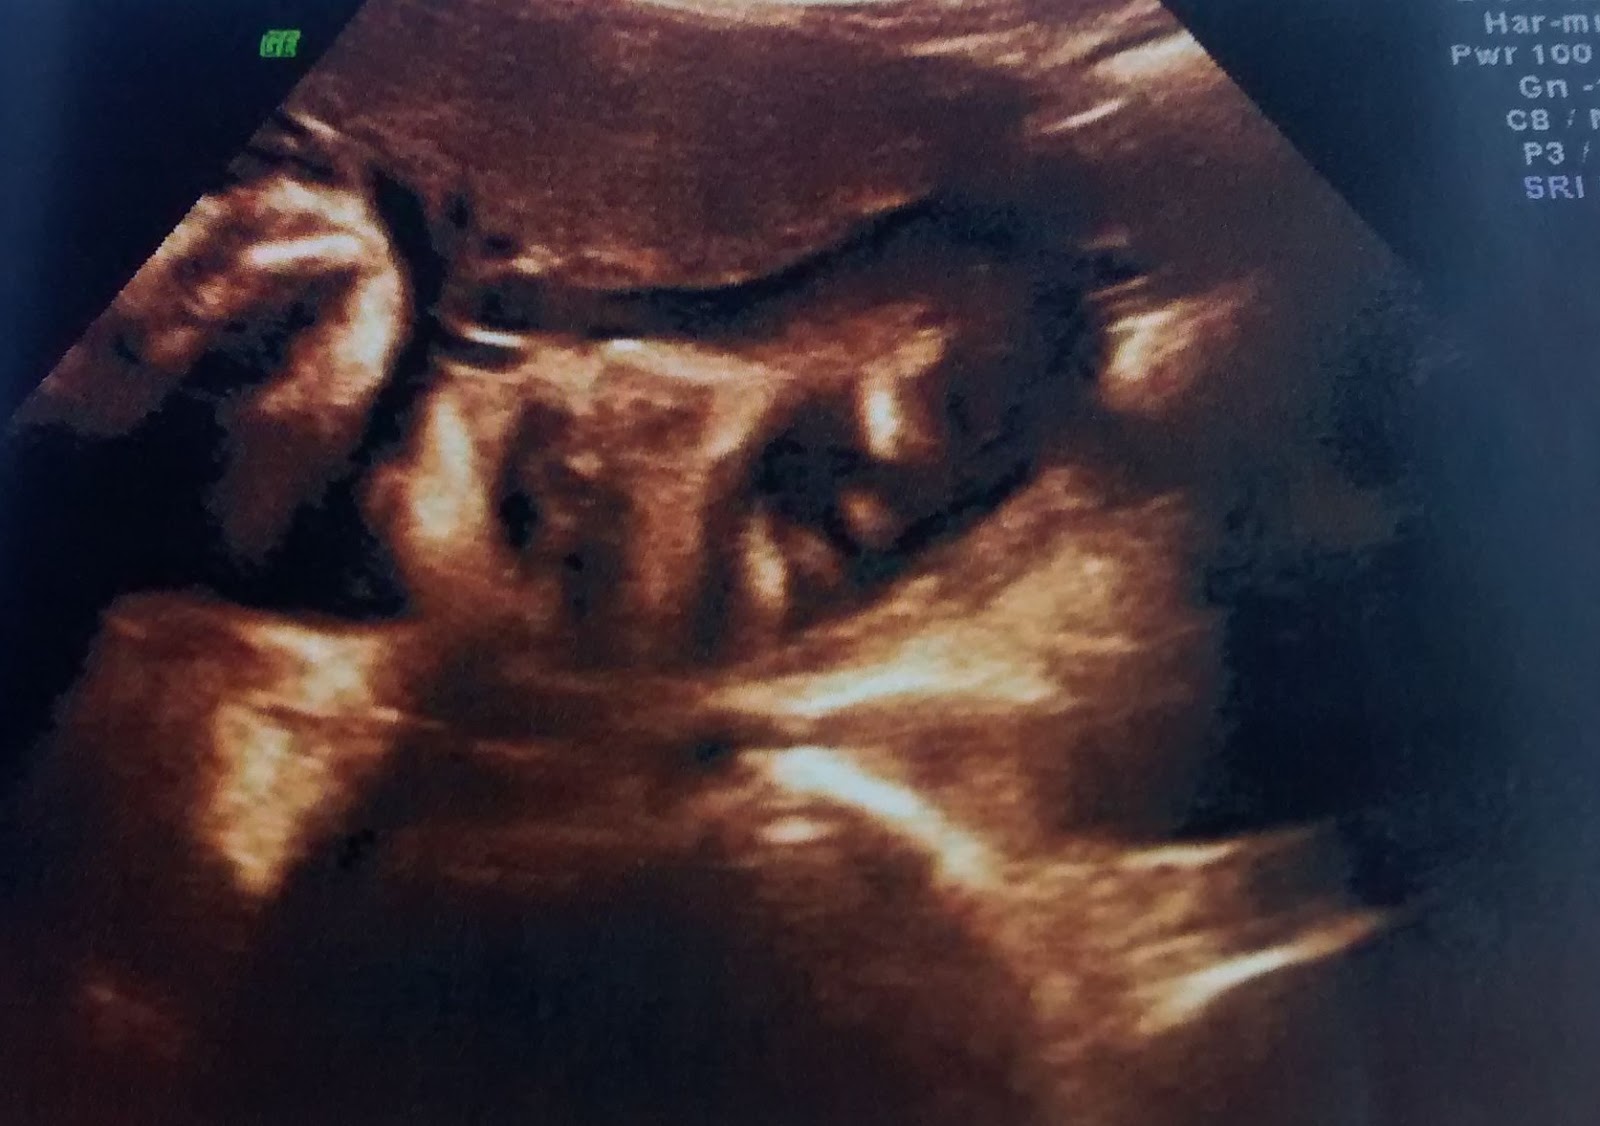

Não víamos nosso pequeno desde 22ª semana, que foi a morfológica que fizemos... desde lá ele cresceu muito....

Hoje meu pequeno já está pesando 3,036kg e medindo 50cm... eita menino grande... até o dia do parto segundo a médica ele pode estar com mais ou menos 3,5 ou 3,8 .... dentro do peso ideal para idade dele.... E ele também já esta na posição certinha para o parto... Viradinho para baixo, as costas esta virada para a direita e os pezinhos estão bem embaixo das minhas costelas do lado esquerdo...

O coraçãozinho como sempre, forte... batimentos a 146bpm ... conseguimos ver muito bem o rostinho dele... e ele ta pura gostosura, com rostinho redondinho e bochechudo....

| Nosso gatinho... olha essa buchechas gente!! vontade de apertar!!! |